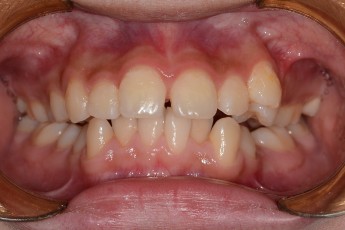

- 덧니교정

Before